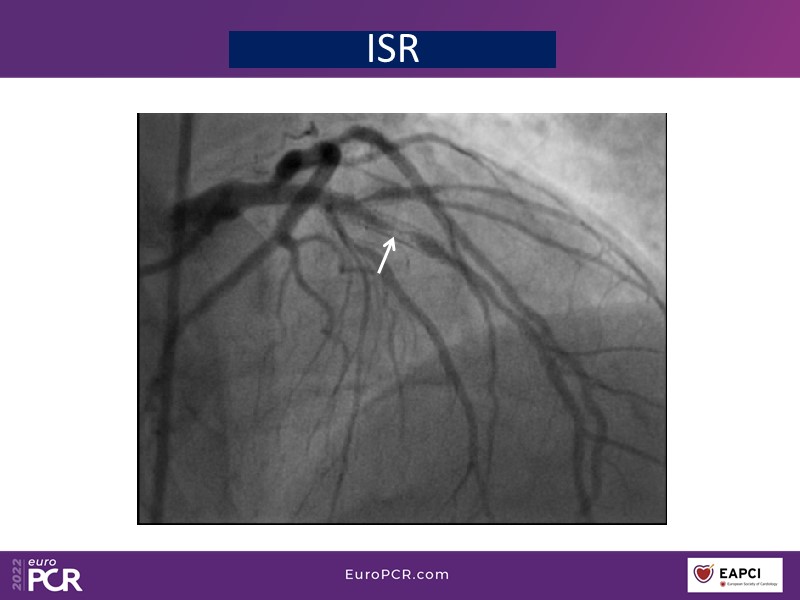

- To find out more about the application and mechanism of a sirolimus coated balloon for coronary artery disease treatment with case presentations in complex settings